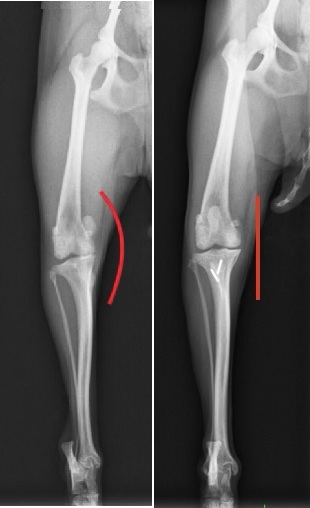

(左)術前レントゲン

(右)術後レントゲン

脛骨粗面転移術はすべての症例に適応するわけではありませんが、脛骨粗面の内側への変位が強い場合にアライメント矯正のため行っています。アライメント矯正とは、膝回りの骨や関節を正常な位置配列にすることで、今回の場合は大腿骨滑車に対して脛骨粗面が正面にくるように外側に動かしています。(レントゲンの赤線)

インプラント(ピン)が残りますが、問題を起こさない場合はそのまま残しておきます。(まれに時間の経過により抜けてくる場合があり、その場合は抜ピンを行います)